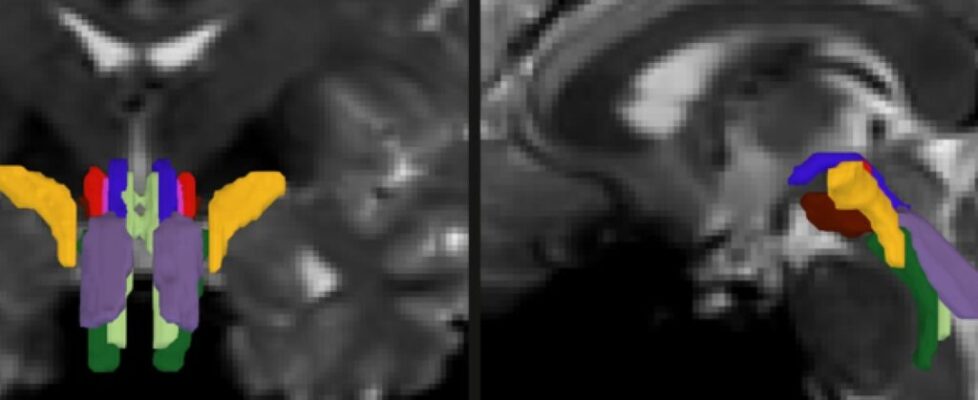

As part of his thesis work to better understand the neural mechanisms that underpin consciousness, Olchanyi wanted to develop an AI algorithm to overcome these obstacles. BSBT works by tracing fiber bundles that plunge into the brainstem from neighboring areas higher in the brain, such as the thalamus and the cerebellum, to produce a “probabilistic fiber map.” An artificial intelligence module called a “convolutional neural network” then combines the map with several channels of imaging information from within the brainstem to distinguish eight individual bundles.

To train the neural network to segment the bundles, Olchanyi “showed” it 30 live diffusion MRI scans from volunteers in the Human Connectome Project (HCP). The scans were manually annotated to teach the neural network how to identify the bundles. Then he validated BSBT by testing its output against “ground truth” dissections of post-mortem human brains where the bundles were well delineated via microscopic inspection or very slow but ultra-high-resolution imaging. After training, BSBT became proficient in automatically identifying the eight distinct fiber bundles in new scans.